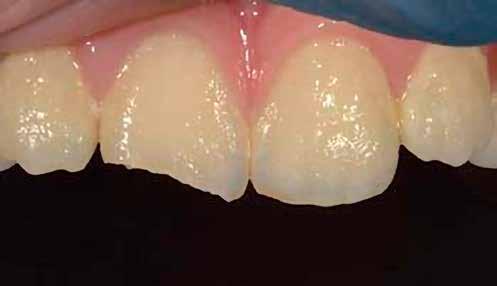

A posterior fogak direkt kompozit restaurációja az egyik leggyakrabban végzett beavatkozás a fogászatban. Az elmúlt években kiemelt figyelem irányult az elérhető eredmények optimalizálására, különös tekintettel a II. osztályú kavitás dobozának (Class II box) kialakítására, és a polimerizációs zsugorodásból eredő feszültség kezelésére. A téma körüli széles körű szakmai diskurzus ellenére van egy olyan lépés, amely gyakran nem kapja meg a kellő figyelmet: a mechanikai formázás protokollja. A mechanikai formázás alatt a restauráció kontúrjának kialakítását, a felesleges kompozit eltávolítását értjük a marginális szélekről, illetve ide tartozik a végső polírozás is. Ez a folyamat három fő lépésre bontható: a felszín oxigén által gátolt, nem polimerizált rétegének eltávolítása, a durva finírozás és a végső polírozás. Jelen publikációban részletesen bemutatjuk ezeket a lépéseket, valamint egy klinikailag hatékony megközelítést vázolunk fel a direkt posterior kompozit restaurációk befejezésére.

A durva finírozás 5 fázisa

A durva finírozás célja a széleken fellelhető felesleges kompozit és peremhiba eltávolítása, hogy a restaurátum széle derékszögű, vállszerű záródásban (90°-os butt joint) végződjön. Emellett feladata az anatómiai széli perem5 kialakítása, amely elősegíti az interproximális területek tisztíthatóságát és a megfelelő okkluzális felszín helyreállítását, valamint annak korrekcióját és optimalizálását.

A durva finírozás menete az alábbi 5 fázisban történik:

2. ábra: A páciens egy nem megfelelő I. osztályú ezüstamalgám töméssel és II. osztályú szuvasodással jelentkezett. A fog izolálása kofferdám alkalmazásával történt.

3. ábra: A preparálás, a bondozás és a kompozit felvitele után. (Megjegyzés: némi kompozit túlfolyás látható a mesiális doboz axiális falain).

4. ábra: A durva finírozás után a restauráció pereme sima és anatómiailag is megfelelő.

6. ábra: I. osztályú restaurációk az első moláris és a második premoláris fogakban. A széleken felesleges kompozit figyelhető meg (piros nyilak jelölik).

12. ábra: A premoláris fogak preoperatív állapota.

13. ábra: A premoláris fogak postoperatív fotója.

14. ábra: Egy moláris fog preoperatív állapota.

15. ábra: Egy moláris fog postoperatív fotója.